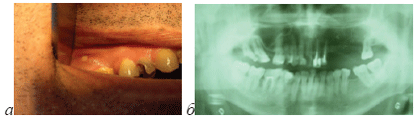

Рис.1. Больной А., применяющий наркотик “крокодил” (дезоморфин), а)оголение кости в области зуба 11, б) на ортопантомограмме больного видно большое количество канал-наполнительного материала, выведенного за верхушку корня зуба, который стал причиной остеонекроза.

Рис.2. Больной Б., применяющий наркотик “крокодил” (дезоморфин), а) оголение кости в области зуба 16, б) на ортопантомограмме больного картина хронического периодонтита зуба 16.